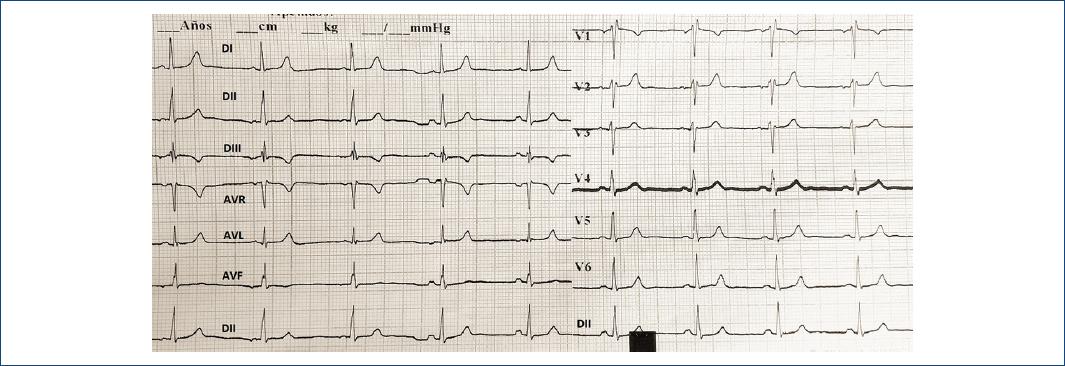

Se presenta el caso de una paciente de 33 años, sin antecedentes de relevancia, que consultó por aparición de fiebre, astenia, anosmia, ageusia y tos seca de 72 horas de evolución. Se obtuvo hisopado nasal para realizar reacción en cadena de la polimerasa para COVID-19, que resultó positivo. Se solicitó tomografía computarizada de tórax que descartó alteraciones del parénquima pulmonar y derrames pleural o pericárdico. Estudios de laboratorio: hematócrito, 38%; hemoglobina, 12 g/dl; leucocitos, 4,900 células/μl; plaquetas, 173,000/μl; y proteína C reactiva (PCR), 4.5 mg/l. Al sexto día del inicio de los síntomas presentó dolor torácico punzante que empeoraba con la inspiración profunda y mejoraba con el cambio del decúbito. La exploración física reveló frote sistólico y diastólico en posición de plegaria mahometana. El electrocardiograma (ECG) demostró taquicardia sinusal a 100 lpm, bloqueo incompleto de rama derecha, segmento ST infradesnivelado de 0.5 mV en DII, DIII, aVF, V5 y V6, y supradesnivelado cóncavo de 0.5 mV en V1 y V2 con T concordante. El análisis de laboratorio registró el nivel de troponina T ultrasensible < 14 ng/l y la creatinina fosfocinasa de 55 UI/l (VN 20/180), mientras que el resto de los parámetros fueron normales. El ecocardiograma transtorácico (ETT) mostró buena función biventricular con engrosamiento parietal sistólico conservado, marcada refringencia pericárdica posterior y ausencia de derrame pericárdico (Fig. 1A y 1B). Se interpretó el cuadro como pericarditis de probable causa viral por SARS-CoV-2, ya que se identificaron tres criterios diagnósticos de inflamación pericárdica en el contexto de dicha infección viral. Se inició ibuprofeno a dosis de 1,800 mg al día, con mejoría, y egresó del hospital a los siete días tras su ingreso.

Figura 1 Ecocardiogramas transtorácicos. A: eje largo paraesternal en el que se observa una marcada refringencia del pericardio en la cara posterior. B: vista subcostal de cuatro cámaras, con refringencia pericárdica en la cara lateral del ventrículo izquierdo.

La pericarditis aguda es un síndrome consecutivo a la inflamación pericárdica, con o sin derrame pericárdico adjunto, y sus causas más frecuentes son infecciones virales y las formas idiopáticas2. Su diagnóstico se establece si se satisfacen dos de cuatro criterios clínicos y siempre debe descartarse miocarditis adjunta mediante determinación de los marcadores de lesión miocárdica2. Cabe destacar que el hallazgo en este caso de hiperrefringencia del pericardio posterior o lateral puede ser un dato inespecífico debido a la mayor distancia de estas estructuras al transductor del ETT, por lo que siempre es fundamental evaluar el pericardio mediante tomografía computarizada de tórax. El tratamiento inicial es la administración de antiinflamatorios no esteroideos y colchicina para reducir la inflamación y el dolor torácico y prevenir la recurrencia, en tanto que los corticoides se reservan ante contraindicación o falta de respuesta al tratamiento inicial2. Los factores relacionados con peor evolución incluyen fiebre, evolución subaguda, derrame pericárdico grave o taponamiento cardíaco, y la falta de respuesta a los antiinflamatorios en los primeros siete días2.